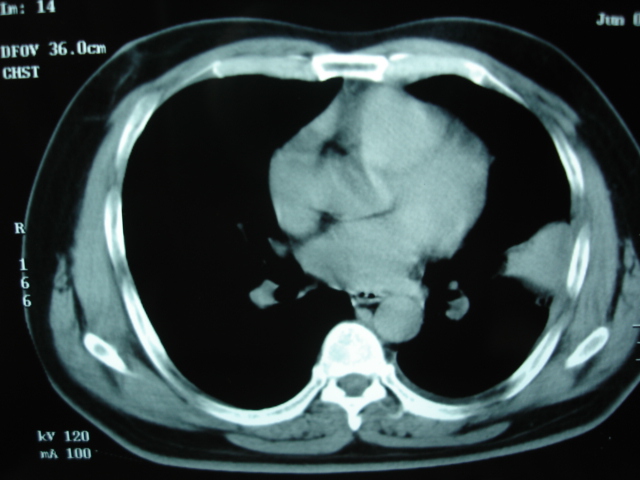

标题: CT21827:男 55 发热,胸痛。抗炎两月。

2009.6.4 2009.6.7 2009.8.21

第一次ct2009.6.4

第二次ct2009.6.7 住院后ect未见异常,查痰(阴性)大量抗菌素抗炎一个月后病灶明显变小,7月5号出院后回家后口服抗菌素45天